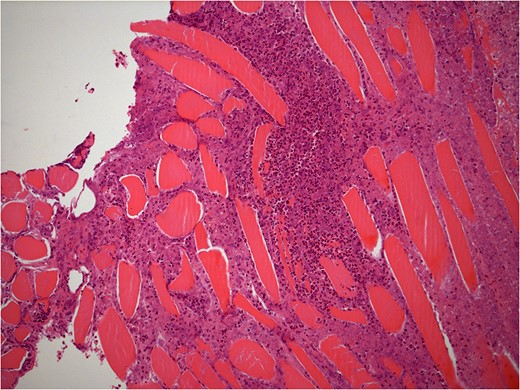

He underwent surgery to explore the tendon where an irregular, cystic, fibrofatty lesion was identified within the tendon (Figs 3–5). This was successfully resected and sent for histology which showed a florid granulomatous and histiocytic response to the suture material, in keeping with a suture granuloma (Figs 6 and 7). There was histological evidence of the abscess extending into the muscle (Fig. 8).

Low power histology slide showing foreign body giant cell reaction to suture material.